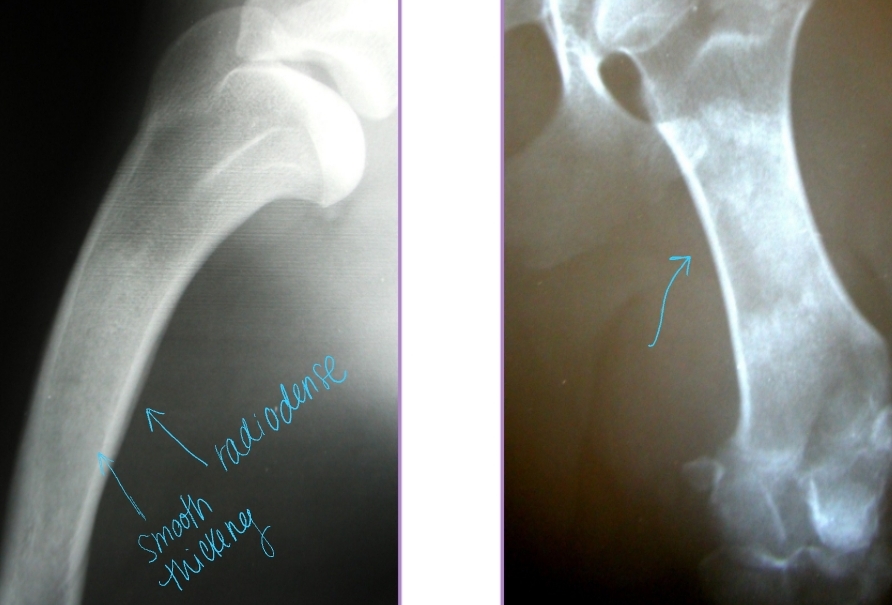

Panosteitis

Et: Disease of endosteum and bone marrow in the long bones

Increased IO pressure due to protein accumulation near nutrient foramen (near major BV), medullary vessels leakage

ulna, humerus, radius, femur, tibia

Forelimb > hindlimb

Sig: 5-18 months, male > female, large breed

Cs: Shifting leg lameness, Lethargic, Pain (cyclic), Anorexia, Fever

Dt:

PE: pain on palpation of diaphysis of long bone

pain receptors in periosteum

Radiographs: Radiodense, patchy infiltrates, Widening of nutrient foramen

Late periosteal response – smooth, thick cortex appearance

Tx: Analgesics, Rest, Self-limiting (1-2w)

relapse can present in other bones